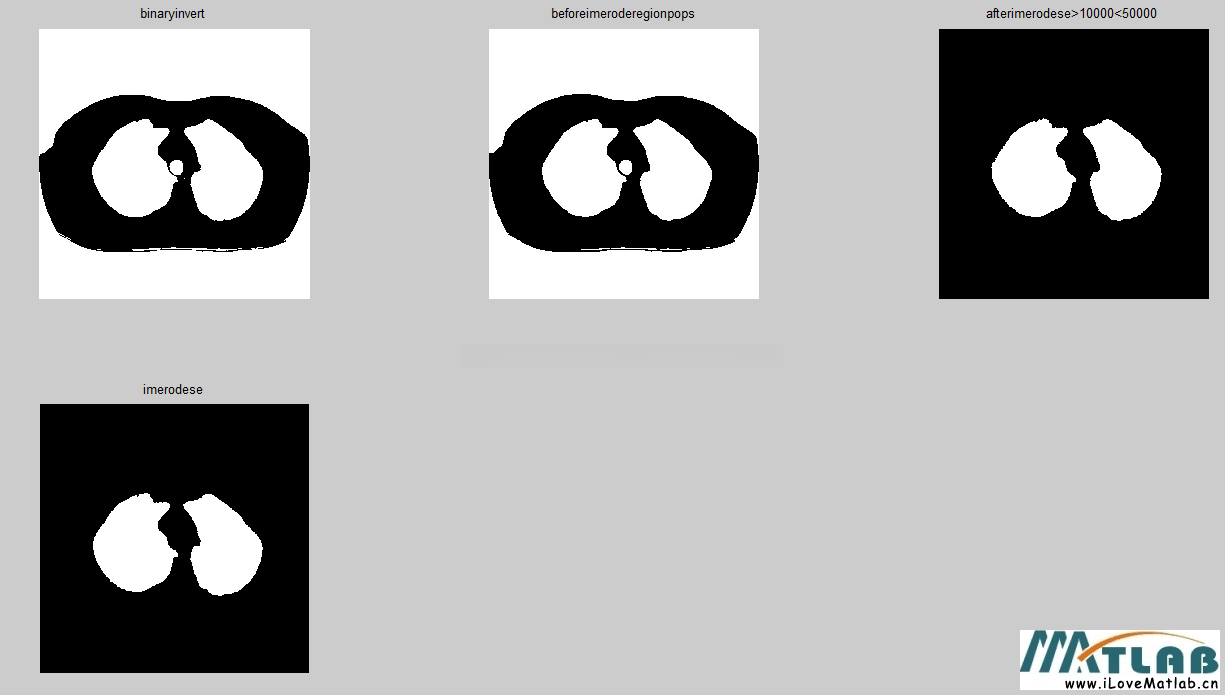

下图(图1)是通过直线扫描方法选取躯干种子点进行区域生长后的效果。为了提取肺实质区域(标记为1和2),我们先将图像进行反转,再进行8连通区域标记,以去除中间肺气管(标记为3)。

但实验发现,无法去除。原因可由图像得知,气管和肺实质在连通标记后粘连在一块。

为此,我们在进行连通标记前先进行腐蚀操作,扩大肺实质和气管间距离。再进行连通标记处理,去除面积较小的气管和面积较大的背景。

figure;subplot(2,3,1);imshow(p);title('binaryinvert');

subplot(2,3,2);imshow(bw);title('beforeimeroderegionpops');

subplot(2,3,3);imshow(bw1);title('afterimerodese>10000<50000');

subplot(2,3,4);imshow(bw2);title('imdilatese');

显示效果如下: